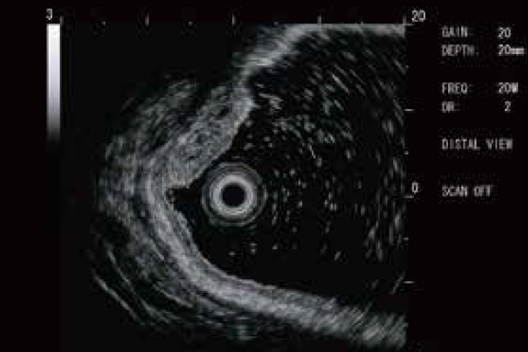

1-قابلیت ورود راحت به sub divisionهای باریک ریه به علت قطر خیلی کم

2-قطر باریک قسمت انتهای پروب امکان دسترسی راحت را به لوب های بالایی برونش فراهم میکند.

| کد محصول | PB-2020 |

| کاربری | ریوی |

| کشور تولید کننده | ژاپن |